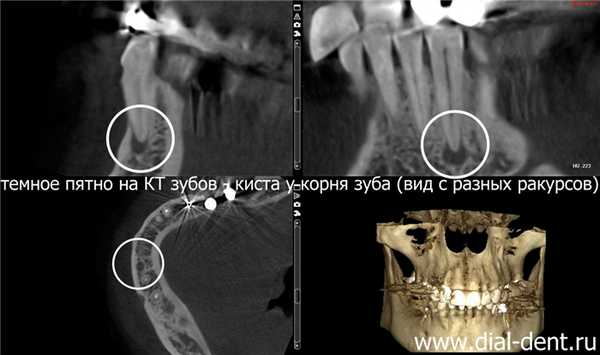

Киста зуба, обнаруженная на компьютерной томограмме зубов

Проблема: пациентке «Диал-Дент» сделали компьютерную томограмму зубов, так как планировалась имплантация зубов. На КТ зубов обнаружена киста зуба на нижней челюсти, которая никак не проявлялась, и пациентка даже не догадывалась, что у корней зуба происходит воспаление, результатом которого может стать потеря зуба.

Диагностика по КТ зубов

Компьютерная томограмма зубов (КТ зубов) - информативный инструмент диагностики для стоматологов. По КТ зубов можно определить точное количество корней у зуба, ответвления, раздвоение корней, наличие ретинированных зубов, наличие воспаления у корней зубов (периодонтит), состояние костной ткани, достаточность кости для установки зубных имплантов, местоположение челюстного нерва и многое другое. В «Диал-Дент» есть собственный томограф, поэтому КТ делается прямо в клинике, за несколько минут. Врач сразу может просмотреть результат КТ и поставить правильный диагноз.

Достаточно часто по результатам КТ зубов выявляются проблемы, о которых пациент даже не догадывался. В данном случае КТ зубов сделано перед установкой имплантов. На КТ зубов обнаружено воспаление у корней, которое со временем могло привести к расшатыванию зуба и его потере. Пациентка даже не помнила, что этот зуб когда-то болел. В данный момент ничего не беспокоило, и только внимательность стоматолога-ортопеда С.В. Цукора помогла вовремя заметить проблему. В «Диал-Дент» перед протезированием зубов всегда делают полную компьютерную томограмму, чтобы видеть состояние всей полости рта и не упустить бессимптомные заболевания, которые могут снизить качество протезирования.

Фрагмент КТ зубов, на котором отчетливо видна киста: